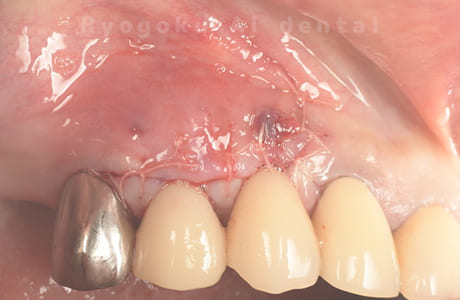

Case06

-

- 原因

- 歯根嚢胞

- 治療内容

- 歯根端切除法

- 治療費用

- ¥110,000

歯根嚢胞が原因でご来院された患者さんです。歯根端切除術を行い、経過良好です。

<リスク・副作用>

外科手術のため、術後に出血、痛みや腫れ、違和感を伴います。口腔内の状態によっては適応できないことがあります。歯根端切除で治らなければ抜歯を検討しなくていけない場合もあります。